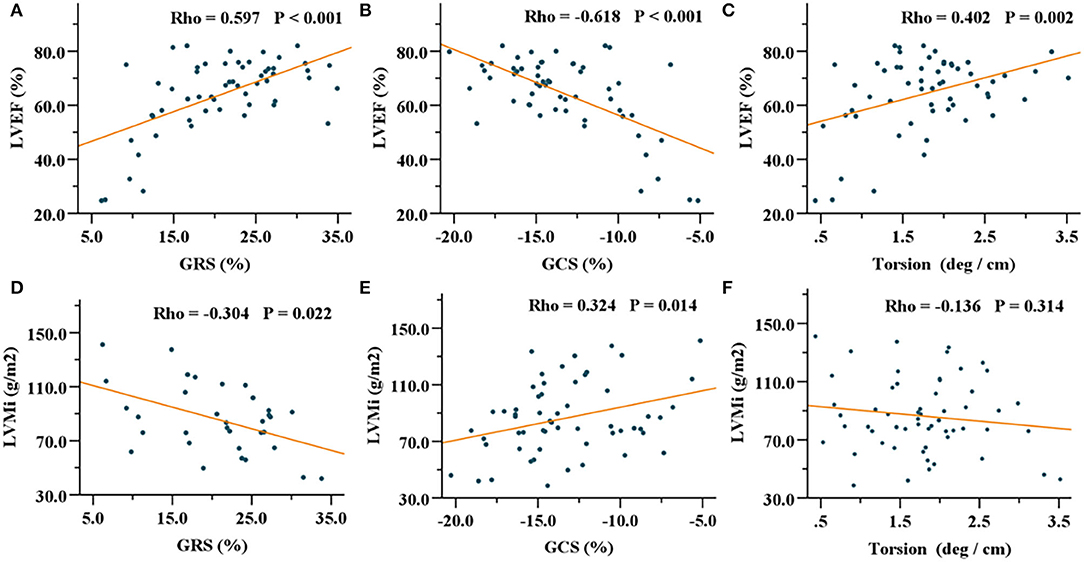

In patients with HCM, GRS, GCS, and GLS showed correlations with LVEF, IVST max, and LVMi (Table 3). Especially, GRS and GCS presented strong correlations with LVEF (GRS, R = 0.597, P < 0.001; GCS, R = −0.618, P < 0.001). In addition, torsion was mildly associated with LVEF (R = 0.402, P = 0.002) (Figure 3). In patients with HHD, GRS, GCS, GLS, and torsion were correlated with LVEF and LVMi (all P < 0.001). In the healthy group, GRS, GCS, and torsion were only associated with LVEF (all P < 0.001).

Figure 3. Correlations of GRS, GCS, and torsion with LVEF (A–C) and LVMi (D–F) in the HCM group. GRS, global radial strain; GCS, global circumferential strain; LVEF, left ventricular ejection fraction; LVMi, left ventricular mass index; HCM, hypertrophic cardiomyopathy.